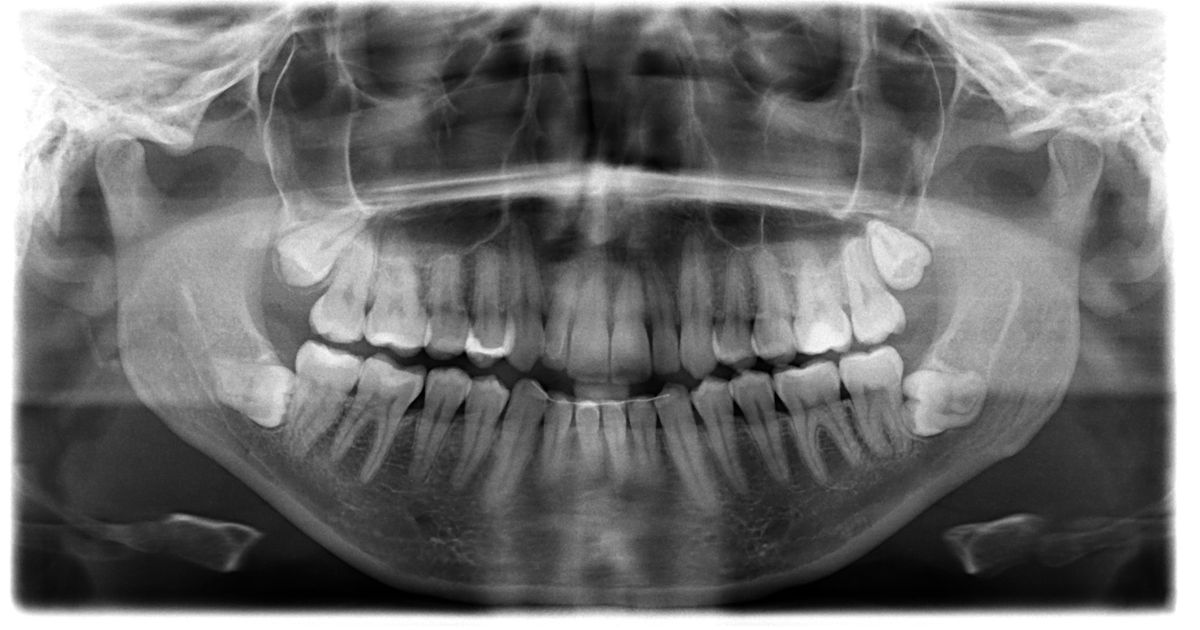

Čovek uradio rendgenski snimak zuba, stomatolozi ostali u šoku: Prizor oborio Ginisov rekord

Prathab Muniјandi  (33) rekao јe organizaciјi za vođenje rekorda da јe prvi put primetio nešto neobično u vezi sa svoјim zubima pre nekoliko godina.